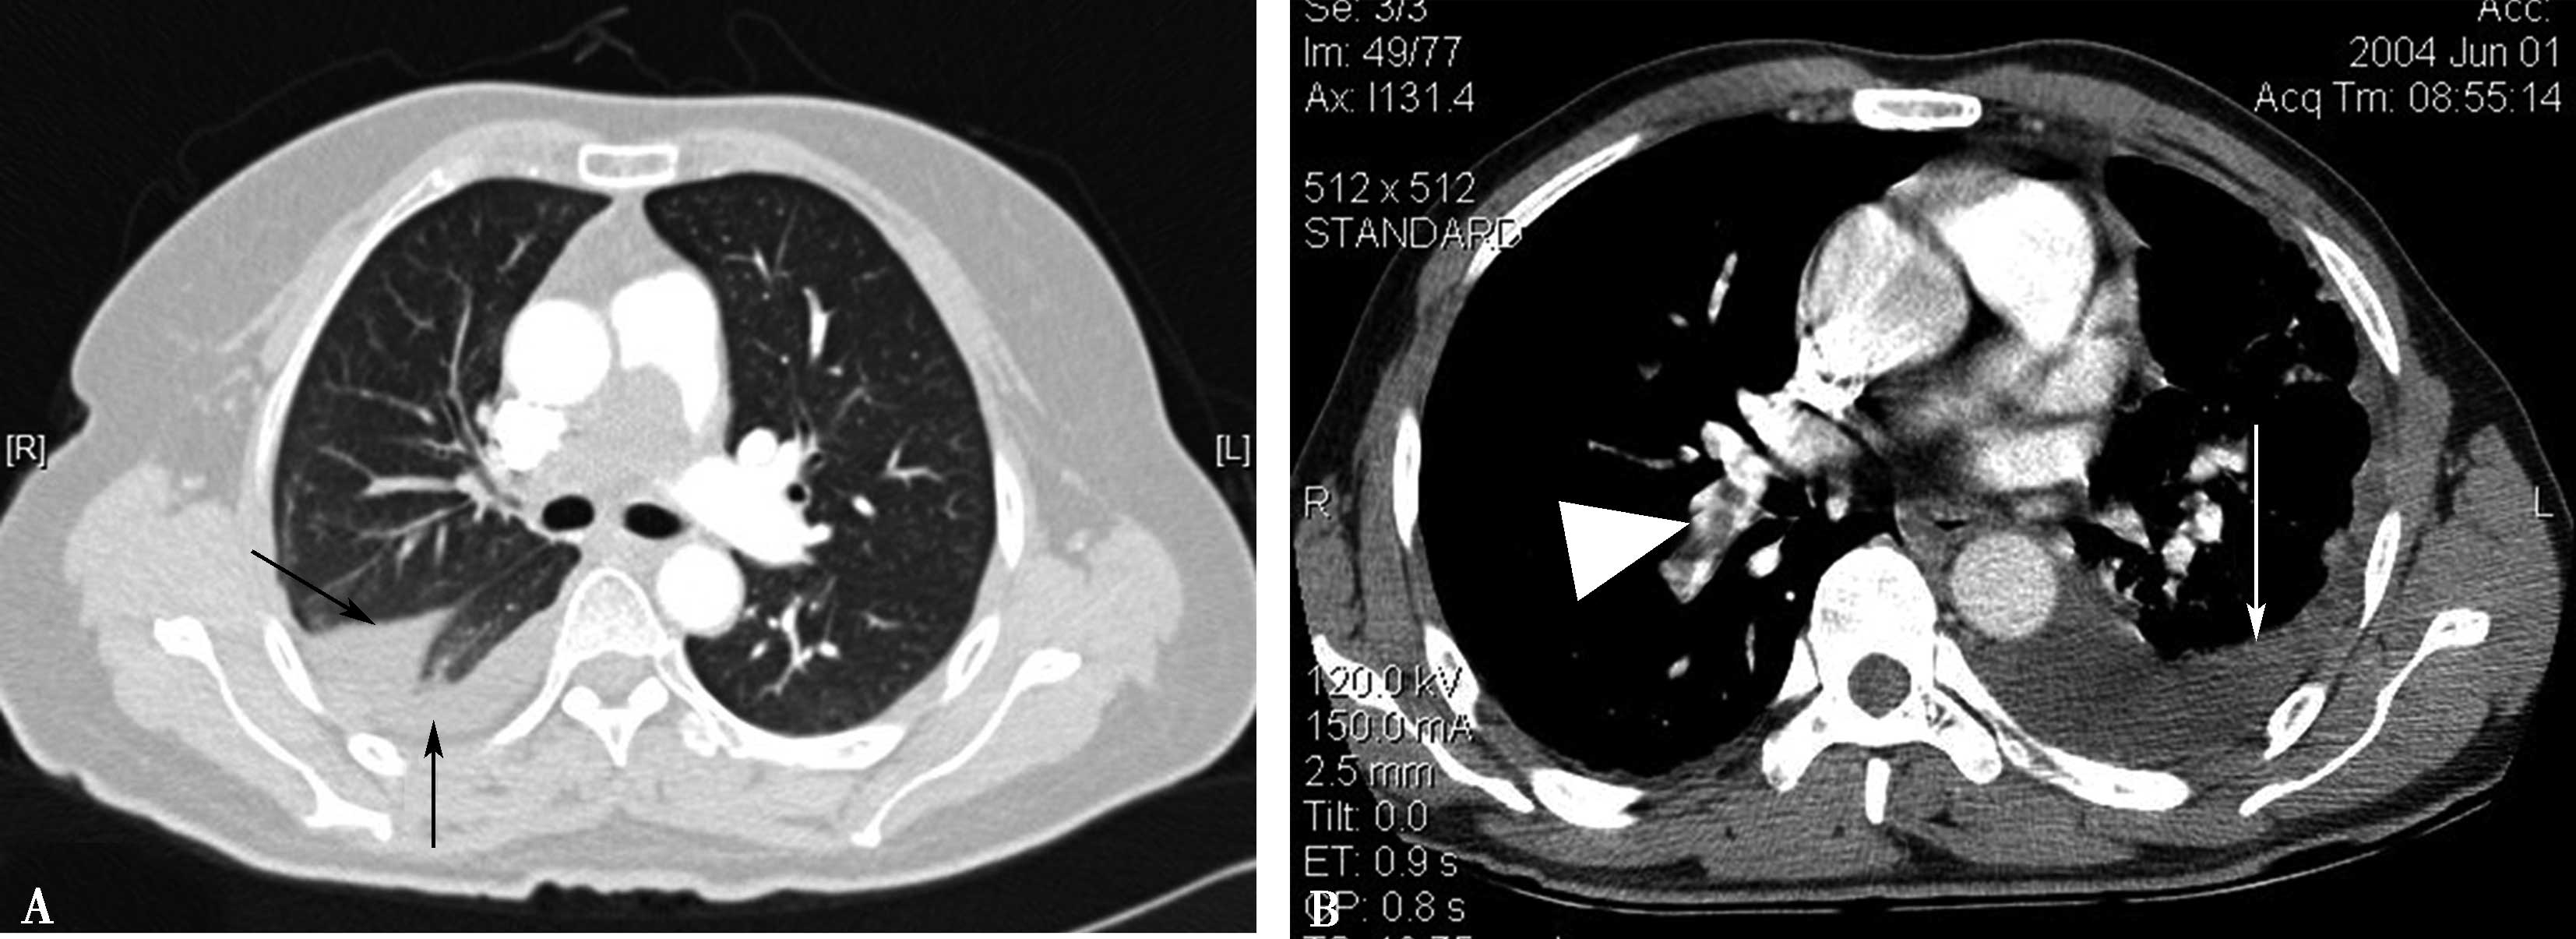

由于血栓栓塞造成栓塞血管区血流灌注减少,与过度灌注区形成明显密度差,造成 “黑白相嵌”现象,称为 “马赛克征”。此为非特异征象,小气道病变亦可形成此种征象(图8-4-4)。

图8-4-4 急性肺栓塞间接征象

A.马赛克征,黑白相间(↑);B.马赛克征,白箭显示相对灌注较好区域,黑箭显示灌注较差区域,呈黑白相间(↑)

3.胸腔积液

可由于肺梗死后胸膜反应所致,首先发生于患侧。右心功能不全也可以胸腔积液,常以右侧胸腔积液为首发(图8-4-6)。

4.肺不张

栓塞局部的肺组织血流灌注减少,区域性的低氧血症和区域性的低灌注可以导致支气管痉挛,肺泡表面活性物质合成的减少,炎症介质引起的血管通透性增加以及肺水肿改变严重时均可出现肺不张;由于胸痛造成的呼吸表浅也是肺不张形成的原因之一。胸腔积液亦可引起被动性肺不张,双下肺多见,强化明显(图8-4-7)。

图8-4-6 急性肺栓塞的间接征象

A.右侧胸腔积液合并斜裂积液(↑);B.左侧胸腔积液(↑);肺栓塞(▲)

图8-4-7 急性肺栓塞的间接征象

A.左下肺不张并胸腔积液;B.双下肺不张并胸腔积液(↑)